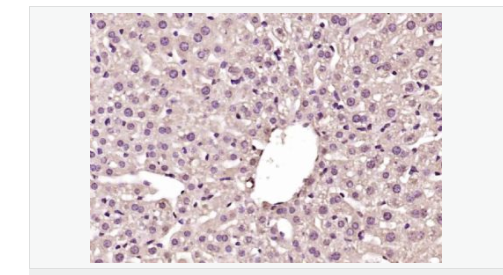

image.png